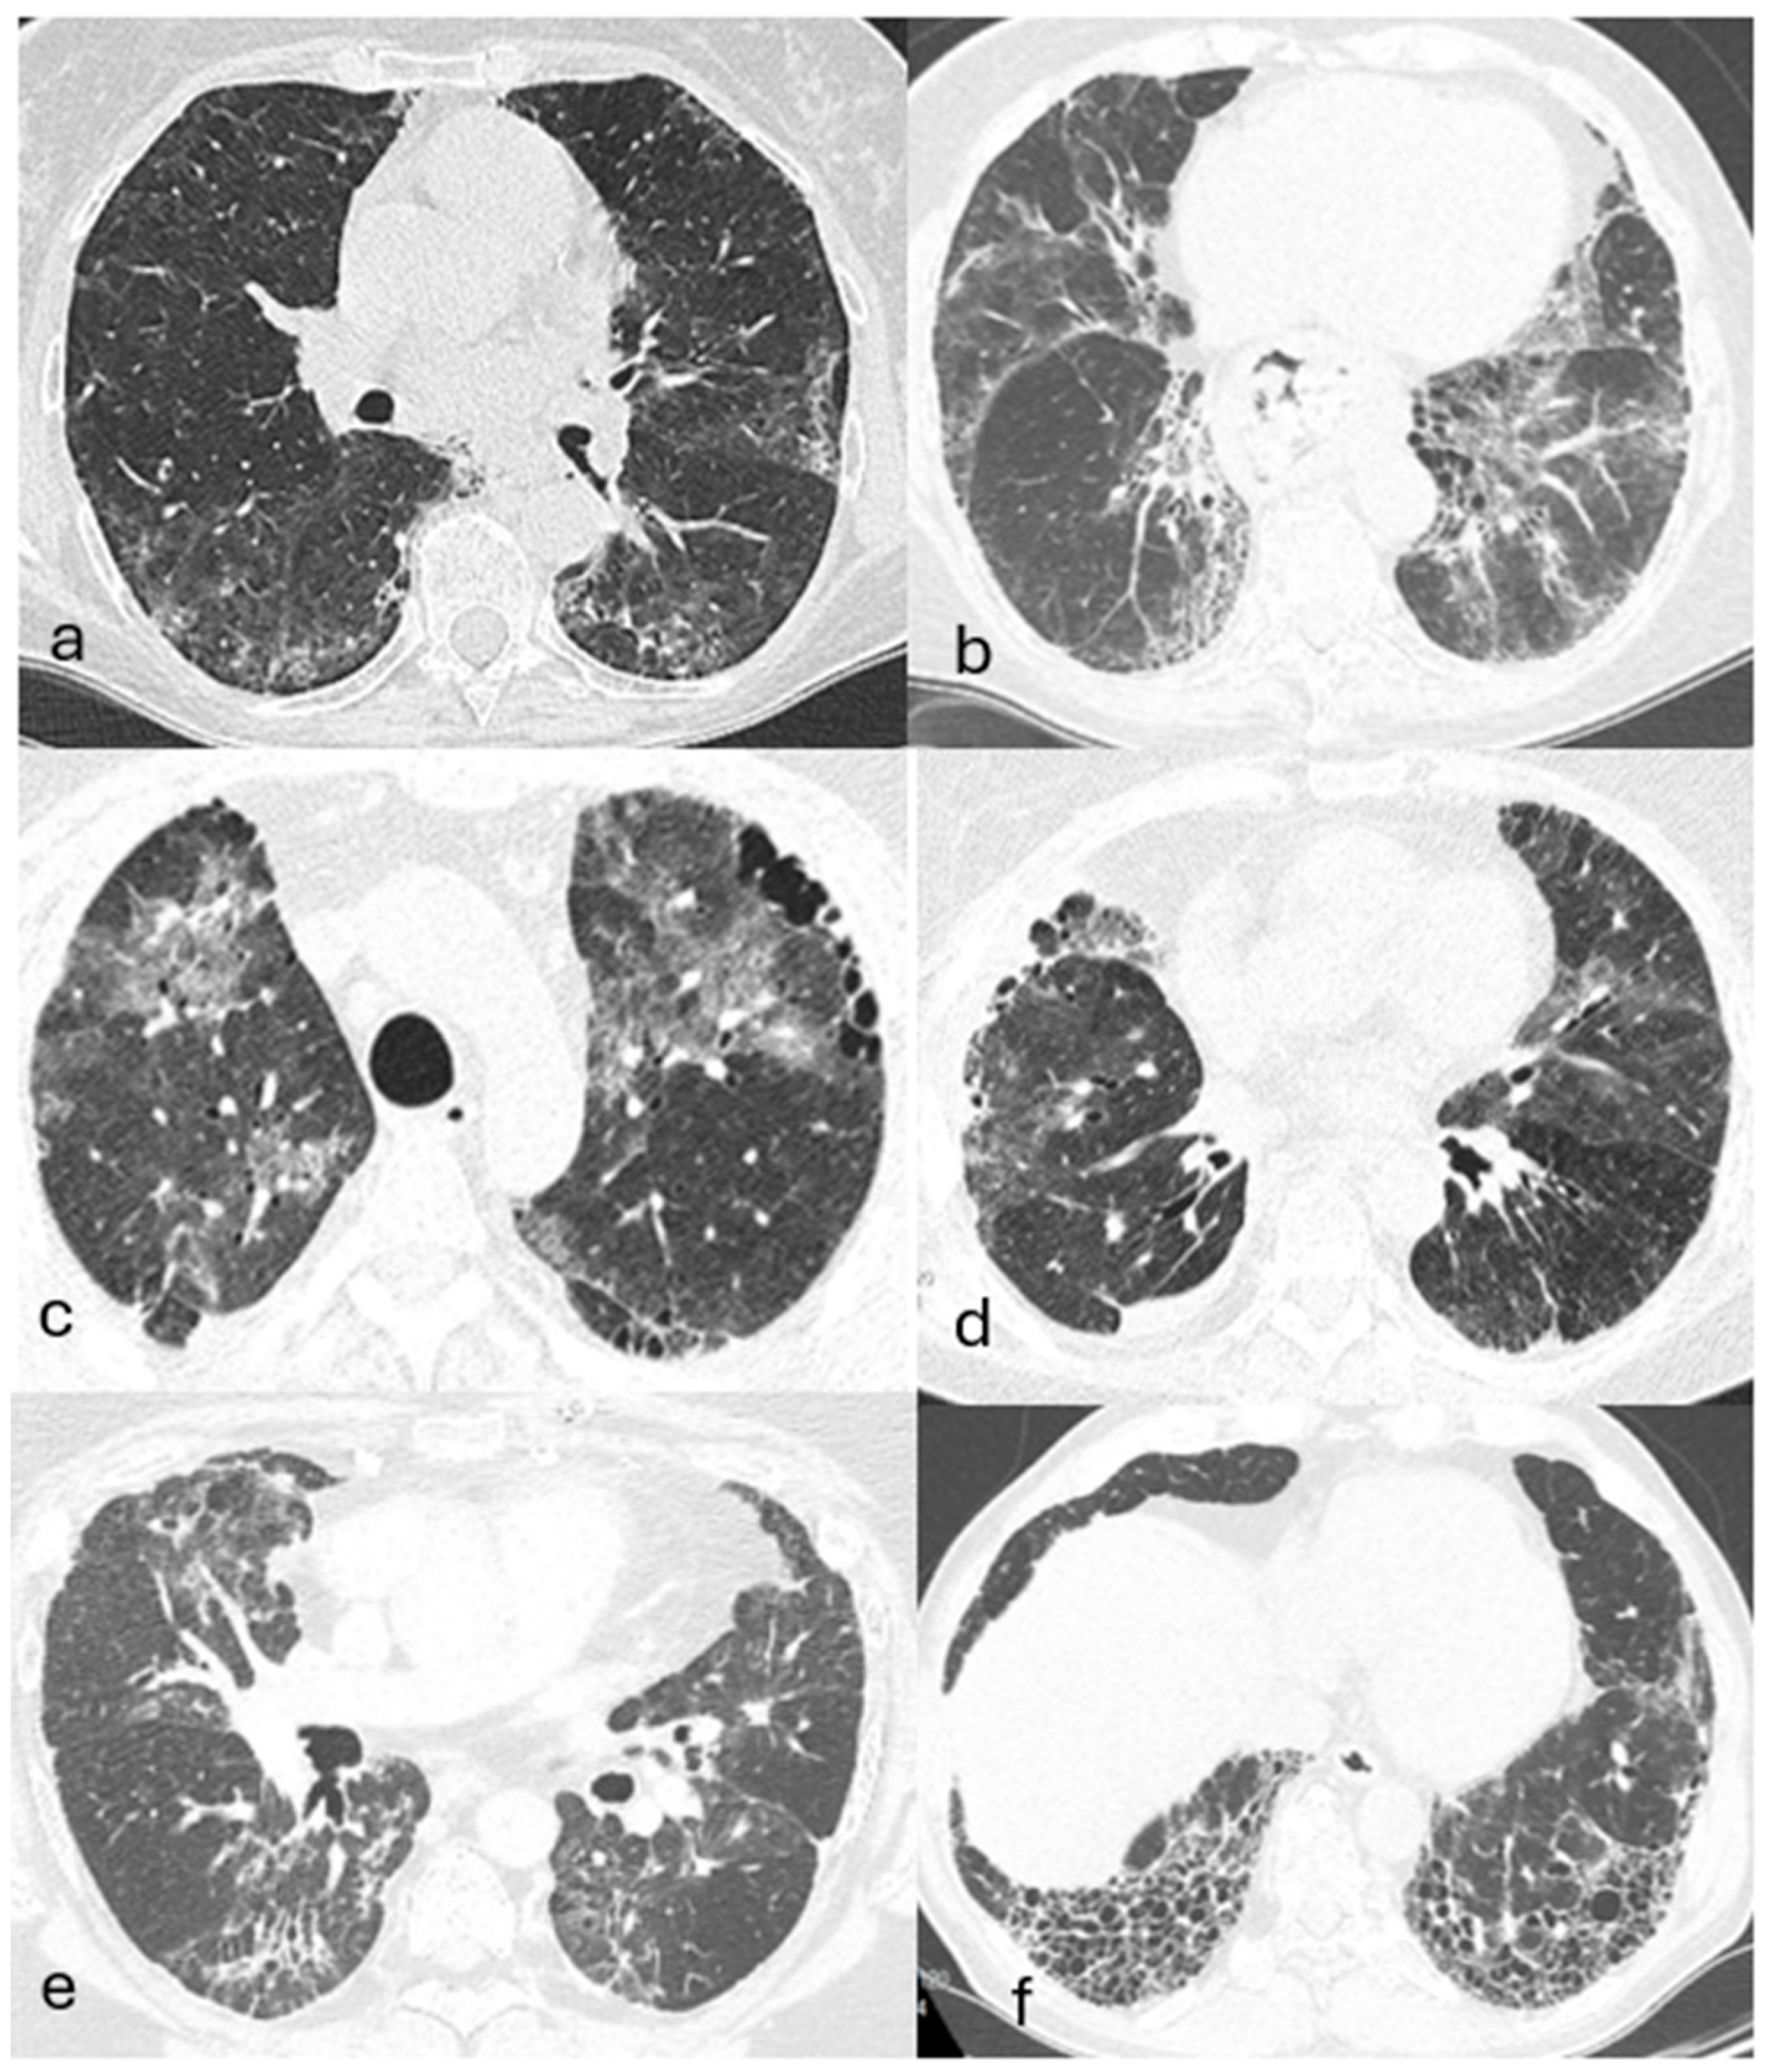

4.4. Imaging